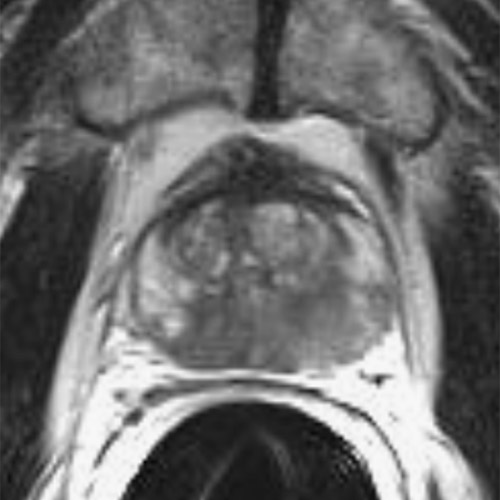

Die Abbildungen zeigen die Behandlung eines Prostatakarzinoms Stadium T2c, N0, M0, Gleason-Score 8, bei einem 63-jährigen Mann. Das Karzinom hat sich über beide Prostatalappen ausgedehnt. Eine fokale Therapie unter Erhalt wesentlicher Anteile gesunden Prostatagewebes war in diesem Fall nicht mehr möglich.

Die Behandlung erfolgte mit 5 Elektroden deren Positionen am Tag nach der Behandlung sichtbar sind (kleine schwarze Kreise). Je Elektrodenpaar wurde eine Ablationszone erzeugt (rote Ellipsen), insgesamt 9 einzelne Ablationszonen. Im Bild nach Kontrastmittelgabe ist die Gesamtablationszone als avaskuläres Gebiet ohne Blutversorgung deutlich zu erkennen.

Das Prostatagewebe wurde komplett zerstört, nur die Prostatakapsel ist erhalten, da sie weitgehen aus Bindegewebe besteht, das durch IRE nicht zerstört wird. Der PSA-Spiegel sank, wie nach einer Prostatektomie, auf 0 ng/ml.